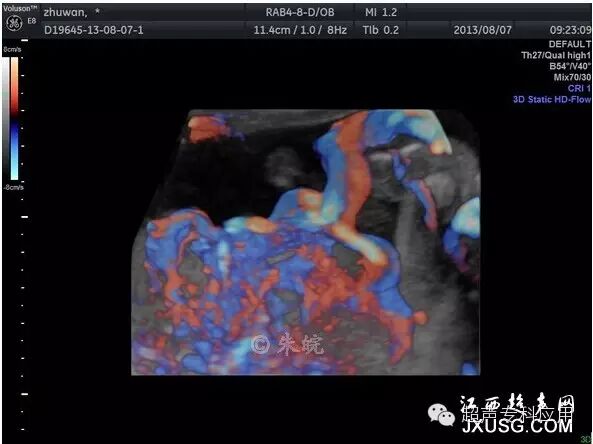

1.9 血管立体结构图及血管分布百分比 立体能量多普勒血流图可显示组织内的血管分布状态、血管吻合隋况,定量分析血流量、血管所占百分比,提供更精确的数据诊断。

胎儿脑颅底动脉环(Willis环)三维能量血管成像

能清晰立体显示大脑中动脉、大脑前动脉、大脑后动脉及交通支构成的Willis环

胎盘脐带插入口能量三维成像,显示胎盘血流分布状况

胎盘脐带插入口能量三维成像,可配合软件计算血管指数